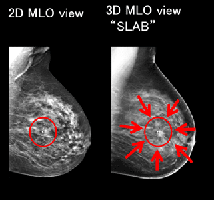

マンモグラフィー 【6,950円】※女性のみ

3Dマンモグラフィ 【8,260円】※女性のみ

3D撮影することで、乳腺の重なった病変を探しやすくなります。撮影は5分程度で終了します。乳房のマンモグラフィ撮影は、2年に一度の検査がおすすめです。